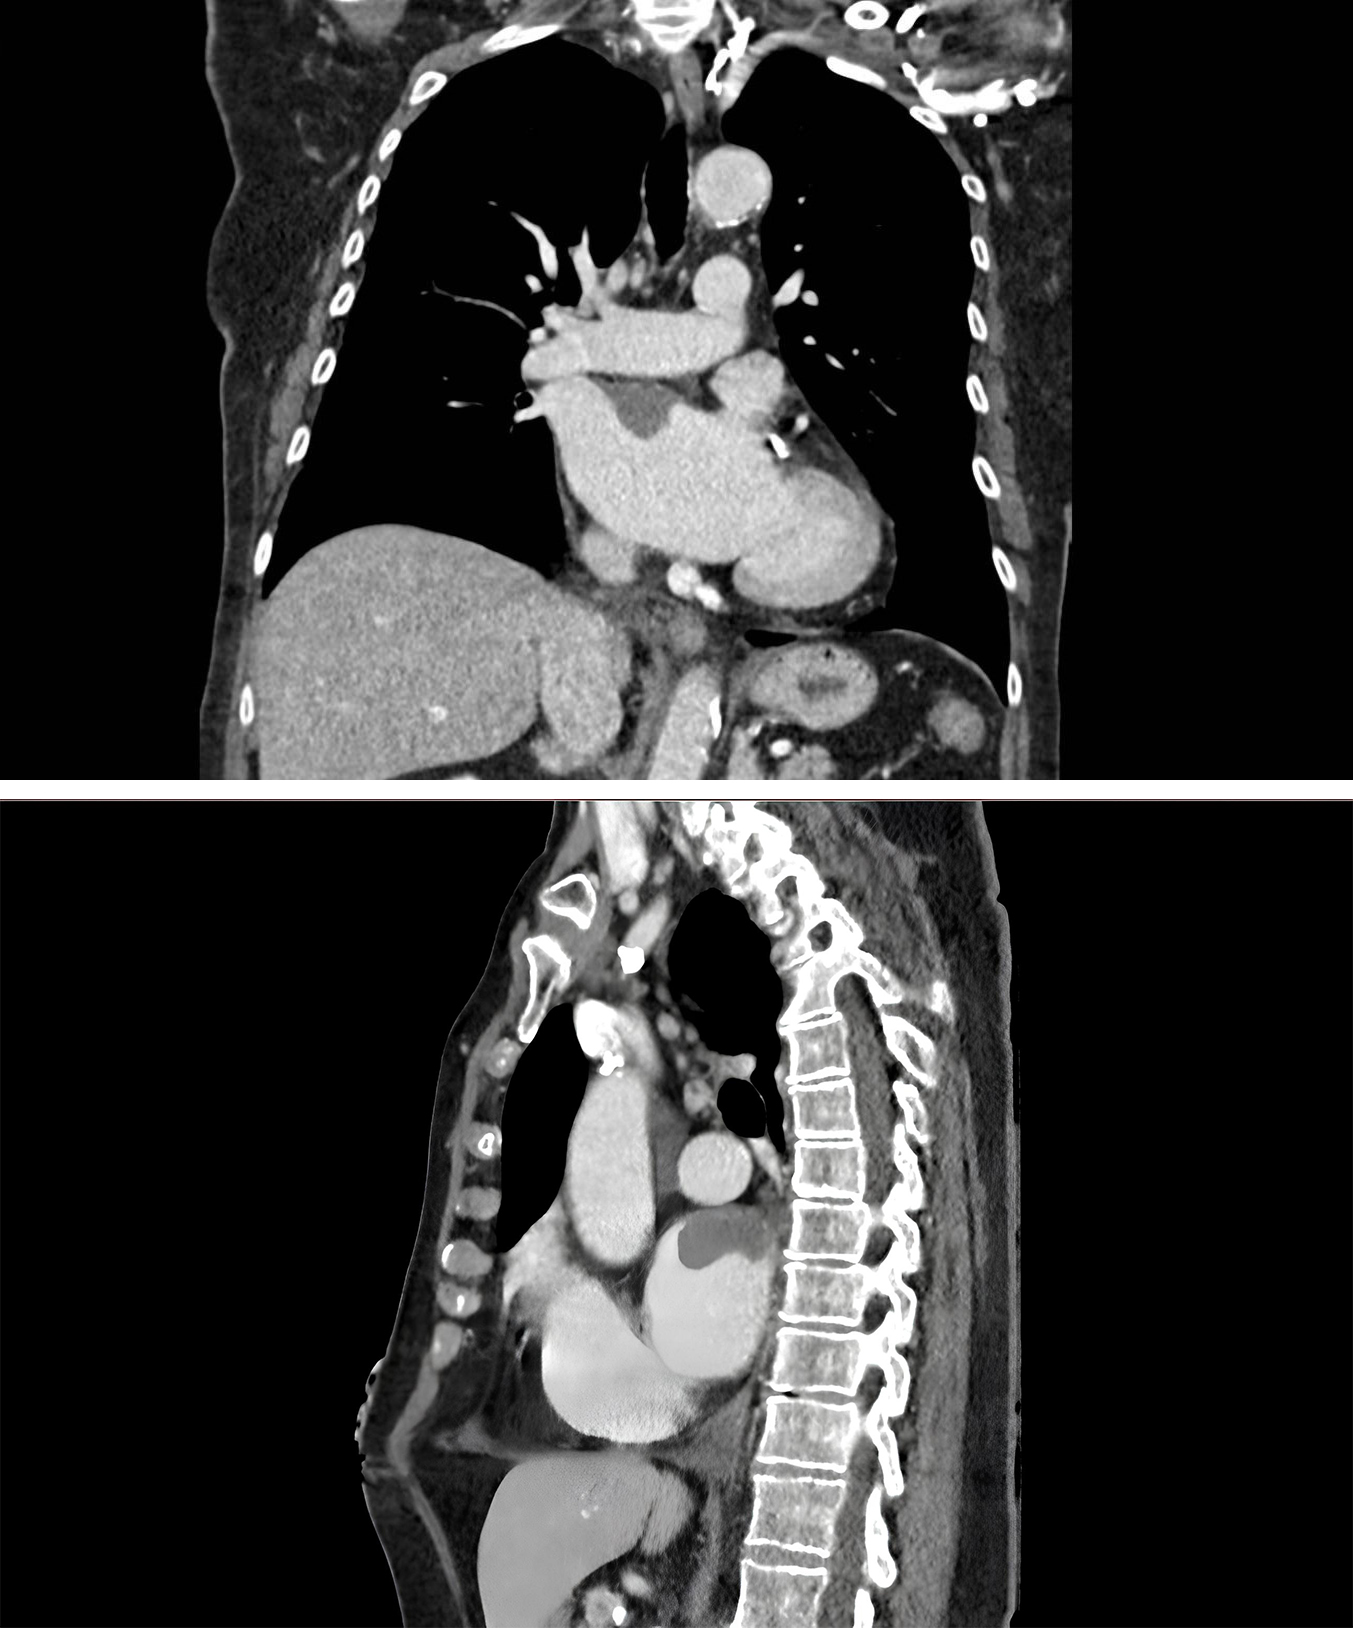

Spectral CT, an evolution of DECT, further enhances tissue discrimination. Hong et al. (2018) [24] demonstrated in 41 patients that dual-energy CT achieved 67% sensitivity and 79% specificity for differentiating thrombi from neoplasms. Their analysis revealed significantly lower normalized iodine concentration in thrombi compared to neoplasms (1.79

Fig. 3. Cardiac CT Demonstrating Right Atrial Thrombus. Axial and sagittal views showing hypodense filling defect in right atrium on contrast-enhanced CT, consistent with thrombus formation.